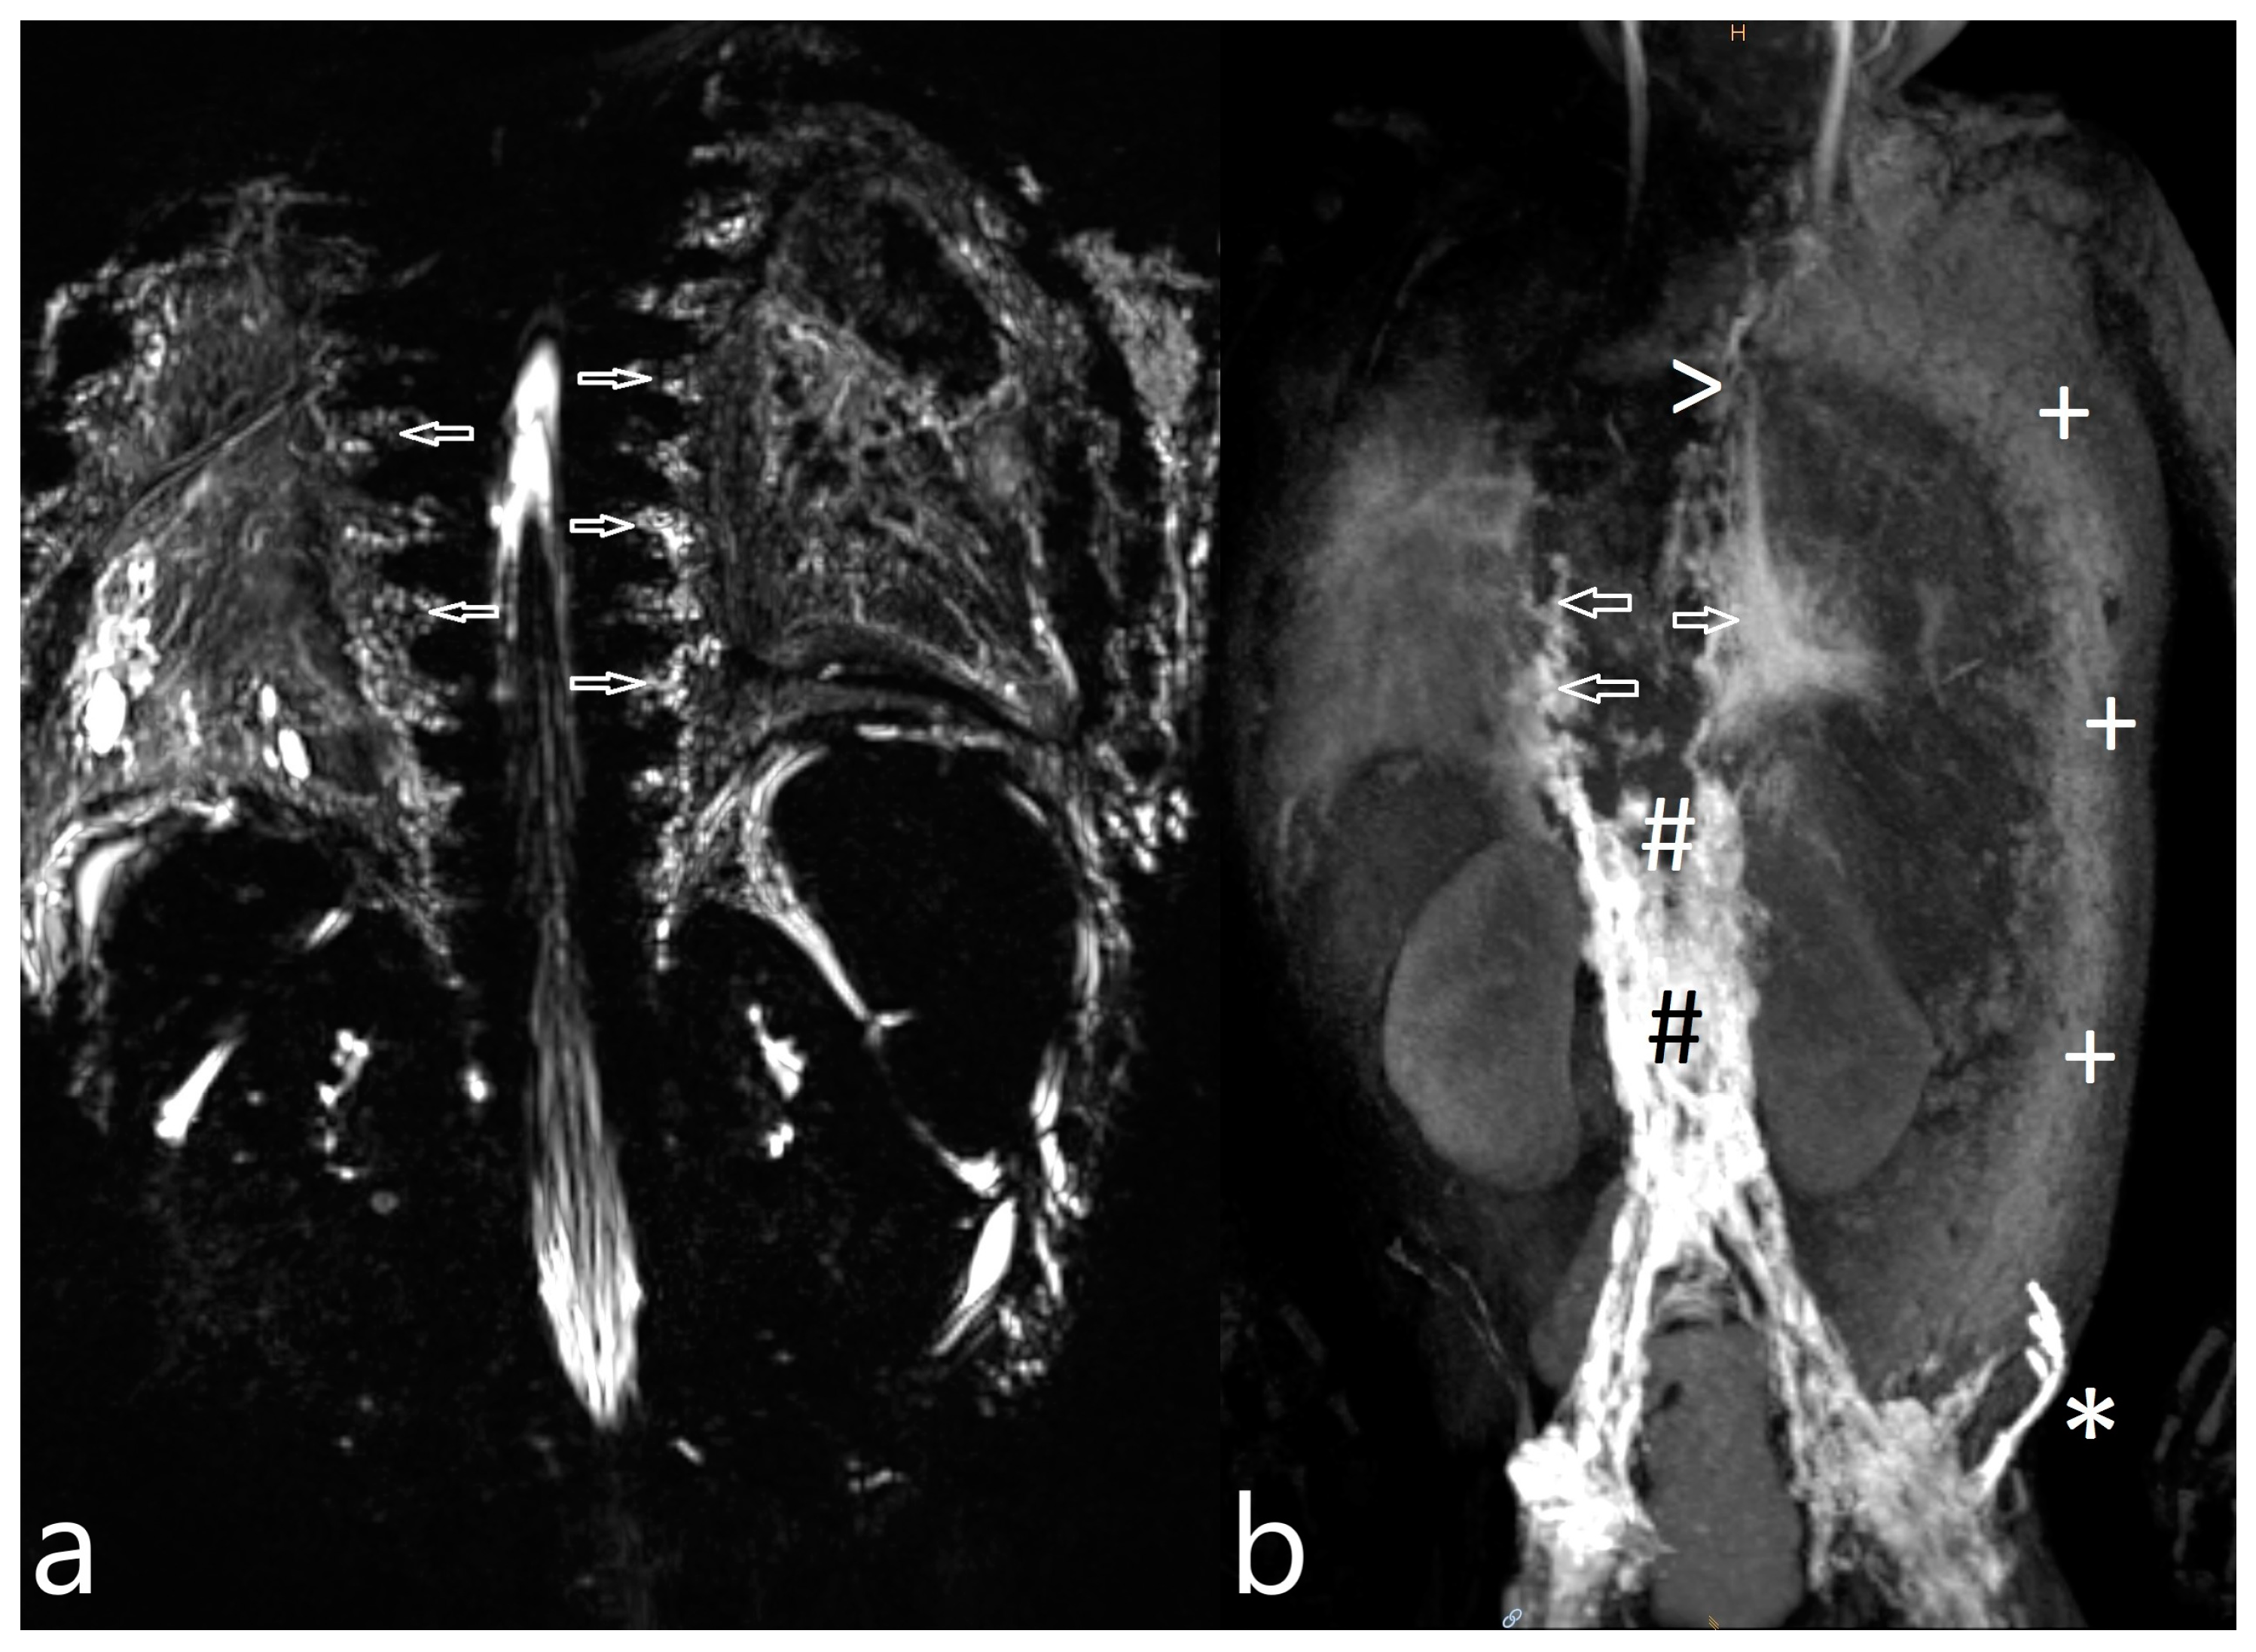

| 5 | 4 | increased signal neck, axilla, mediastinum, hilum and body wall, pleural effusion le > ri, ascites | TD intact, retrograde flow towards hilum le, dermal backflow in abdominal wall, reduced central flow | CLFD | no fistula visualized | CT revision, furosemide, etacrynic acid, captopril, | MCT diet | resolution (21/44/63) |

| 6 | 4 | increased signal neck, axilla, mediastinum, hilum and body wall, pleural effusion, ascites | TD intact, delayed central lymphatic flow, retrograde flow towards pleural space ri > le, hilum le, dermal backflow in thoracic and abdominal wall | CLFD | no fistula visualized | CT revision | not indicated | died (20/-/-) |

| 7 | 4 | increased signal neck, mediastinum and hilum, bilateral pleural effusion | TD intact, retrograde flow towards mediastinum and lung parenchyma bilateral | PLPS | TD bilateral TV 2 | CT revision, levosimedane | MCT diet, sandostatin, levosimedane | resolution (31/63/75)) |

| 1 | 4 | increased signal neck, mediastinum, hilum, perihilar, interstitial lung parenchyma, pleural effusion | abnormal, perfusion to the lung, intercostal flow, dilated lymphatic networks in neck, mediastinum, hilum and perihilar | in the right apical lung | diuretics, sildenafil, non-invasive ventilatory support | lymphatic intervention | Resolution of CT (FU: 10 m, cessation of ventilatory support. |

| 3 | 4 | increased signal neck, mediastinum, hilum, interstitial lung parenchyma, body wall edema, pleural effusion, ascites | abnormal, perfusion to the lung, intercostal flow, dermal backflow, | TV 6–9 bilateral into the lung | diuretics, sildenafil, MCT diet, non-invasive ventilatory support | no | persistent chylothorax, respiratory support |